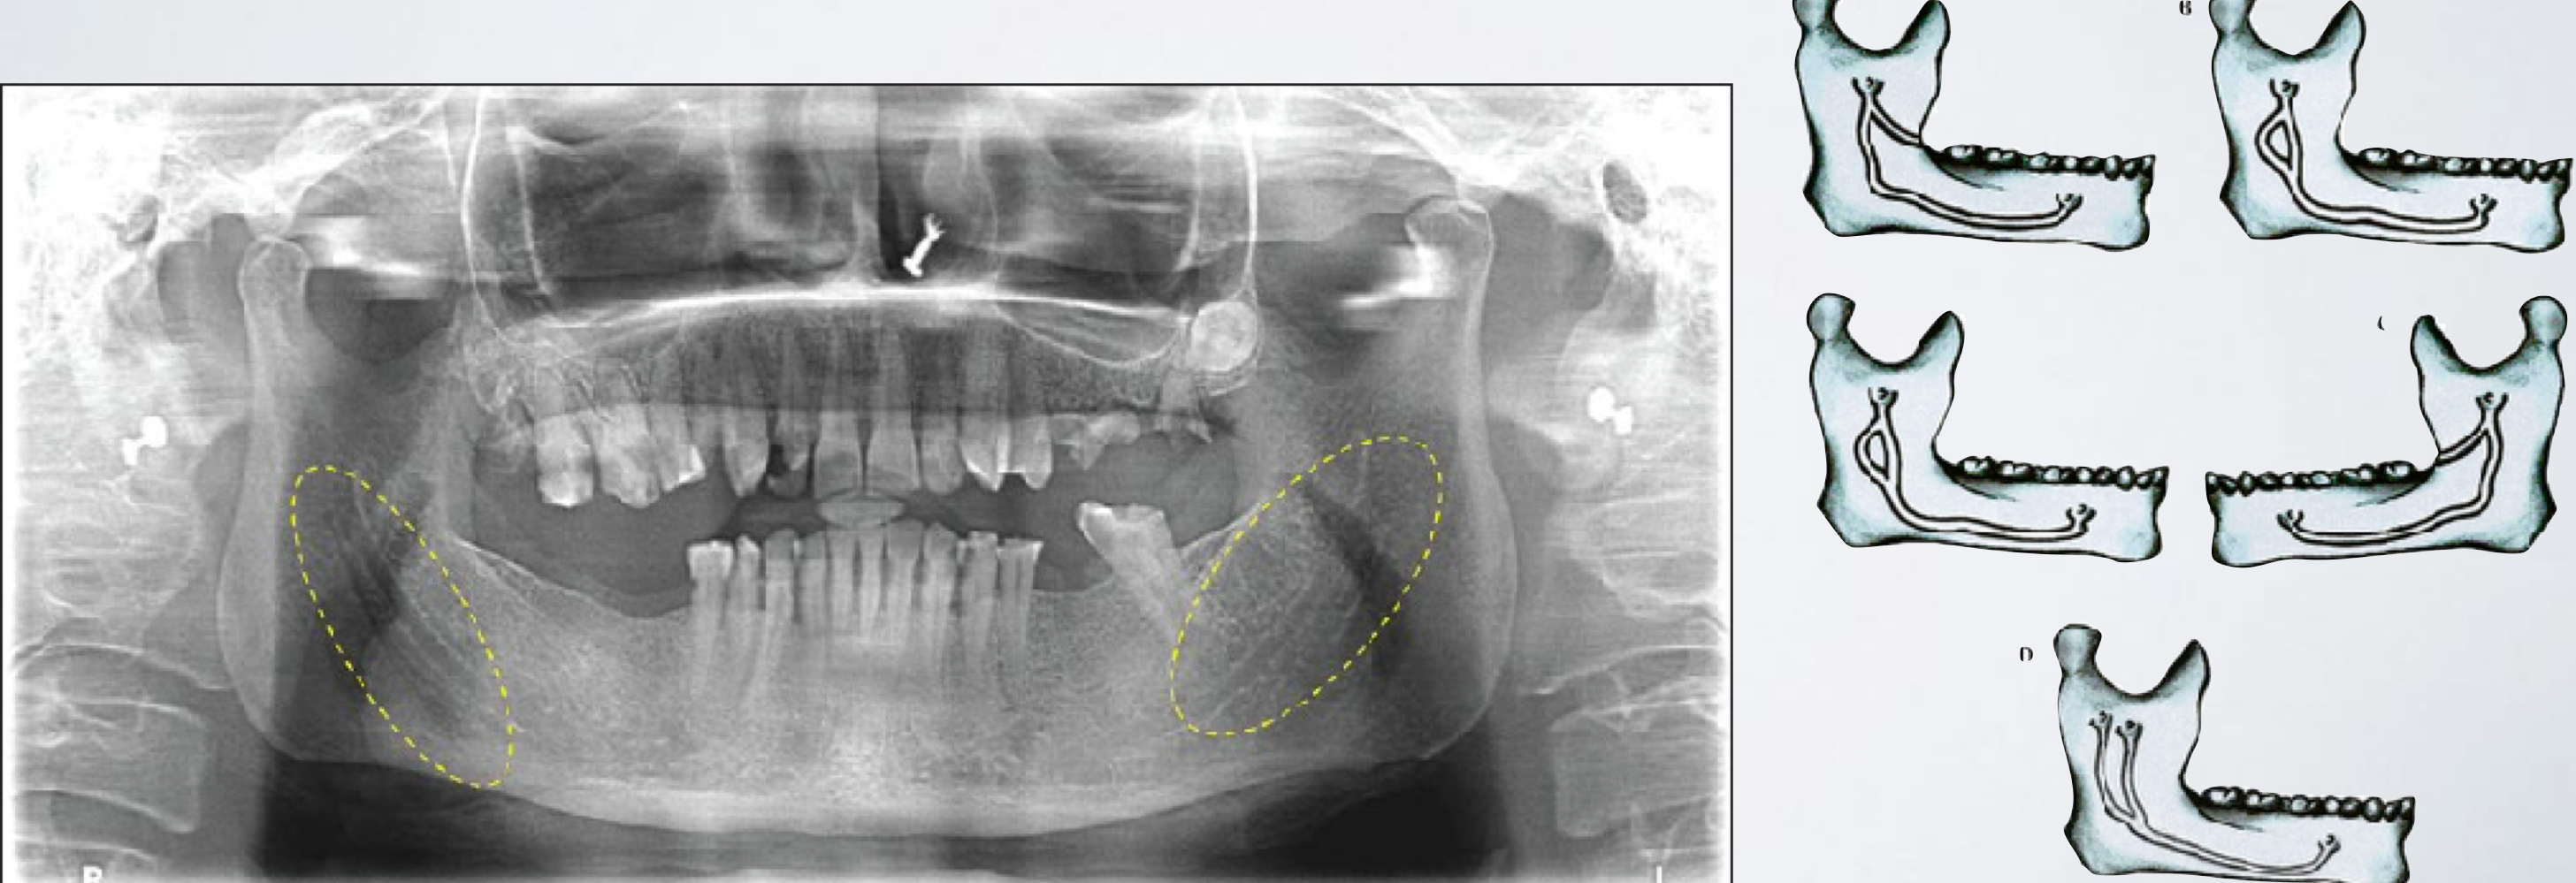

describe failure of IAN block and relationship to bifid inferior alveolar nerve/canal

A second mandibular foramen may exist

To correct: second injection inferior to the normal anatomical landmark